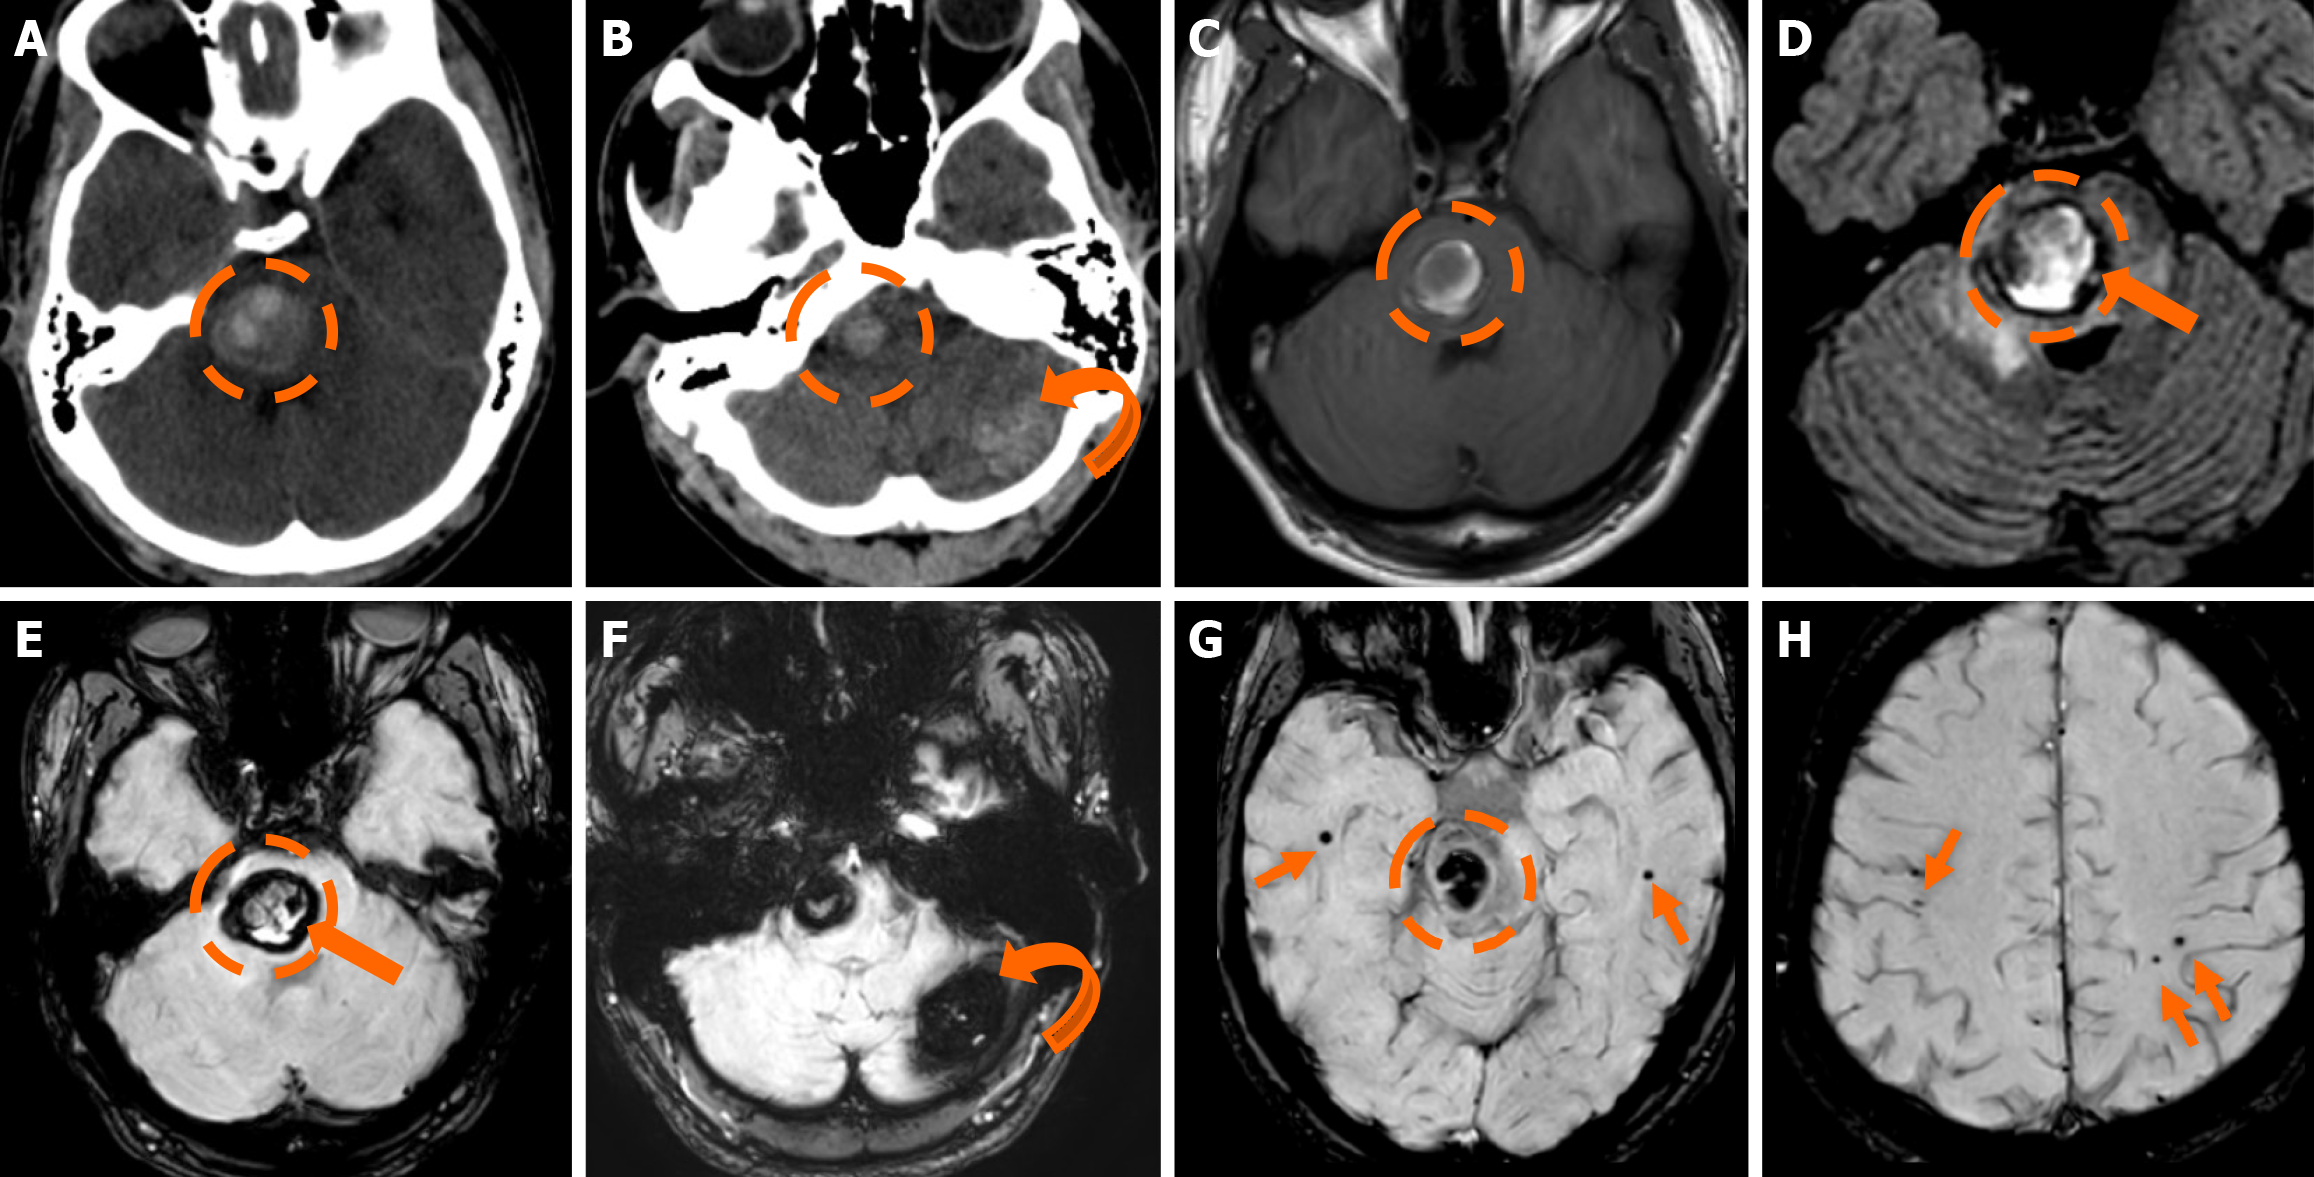

Functional MRI (fMRI) depends on blood oxygen level-dependent contrast, and changes are attributed to both extravascular tissue and local capillaries and veins. Theoretically, DVAs can contribute to the fMRI signal and can potentially lead to pseudoactivations during presurgical mapping[58]. Various examples of DVAs on CTs and MRIs are shown in Figures 1 and 2.

The clinical applicability of the Zabramski classification is still being investigated. A retrospective cohort study evaluating the imaging evolution and clinical trajectory of 255 untreated patients with sporadic CMs over a follow-up period of approximately five years provided evidence that the Zabramski classification may facilitate risk stratification and contribute to treatment planning, particularly in determining the necessity for surgical intervention[89]. Furthermore, a recent study by Saari et al[88] established an association between the radiological characteristics of the Zabramski classification and their clinical relevance, emphasizing that type I lesions have a higher likelihood of becoming symptomatic. Nikoubashman et al[90] suggested an additional category (type V lesions) accounting for cavernomas presenting with gross extralesional hemorrhage. Various examples of CMs on CTs and MRIs, including familial cerebral CM cases, are shown in Figures 4, 5 and 6.

Imaging findings in coexistent DVAs and CMs will be the combination of those described for each malformation separately. Awareness of the possibility of their coexistence may prove invaluable in clinical practice. This is because recognition of a DVA close to a brain hemorrhage may raise suspicion for an underlying CM as the most likely etiology. Additional examinations and follow-up imaging following hematoma resolution will further enhance diagnostic confidence. Figures 8, 9, 10 and 11 illustrate clinical examples in which identifying the synchronous presence of a DVA adjacent to a brain hemorrhage (or suspected brain hemorrhage) enabled the diagnosis of a probable underlying CM as the most likely etiology, thereby avoiding unnecessary examinations or interventions.